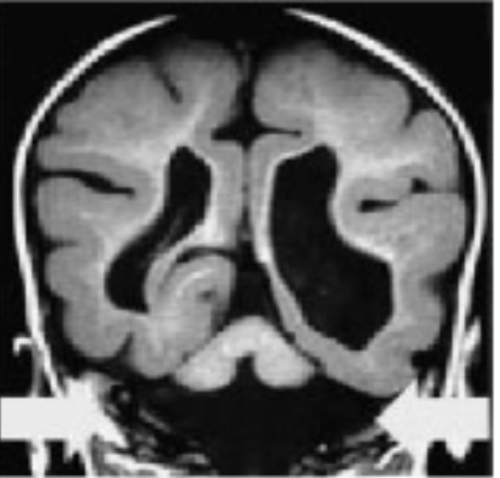

Mutations affecting migratory signals disrupt cortical organisation

Eg If reelin gene is mutated=lissencephaly→severe learning difficulties and epilepsy

This is as the cells intended to be superficial end up in deep layers and vice-versa. Therefore cortical layers= inside out + the cortex itself is too thick